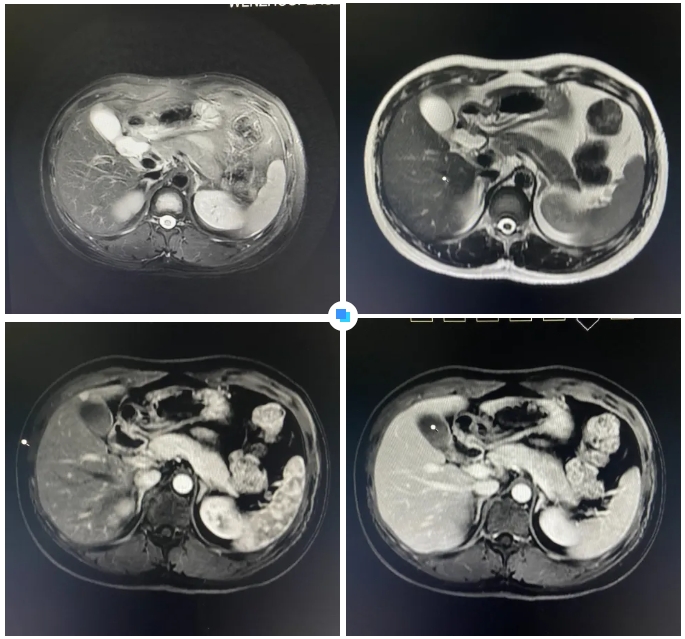

在被問到如何發(fā)現(xiàn)隱藏如此深的病灶時,和平國際醫(yī)院影像中心執(zhí)行主任侯文杰講到,該病灶在平掃T1、T2項都非常不清楚,只有彌散加權的情況下,病灶區(qū)域顯示出輕微的高信號,這一細微線索引起了他的高度關注。

隨后的增強核磁掃描發(fā)現(xiàn),在動脈期病灶顯著強化,而在門脈期明顯減退,這一特征與微小肝癌的表現(xiàn)高度吻合。